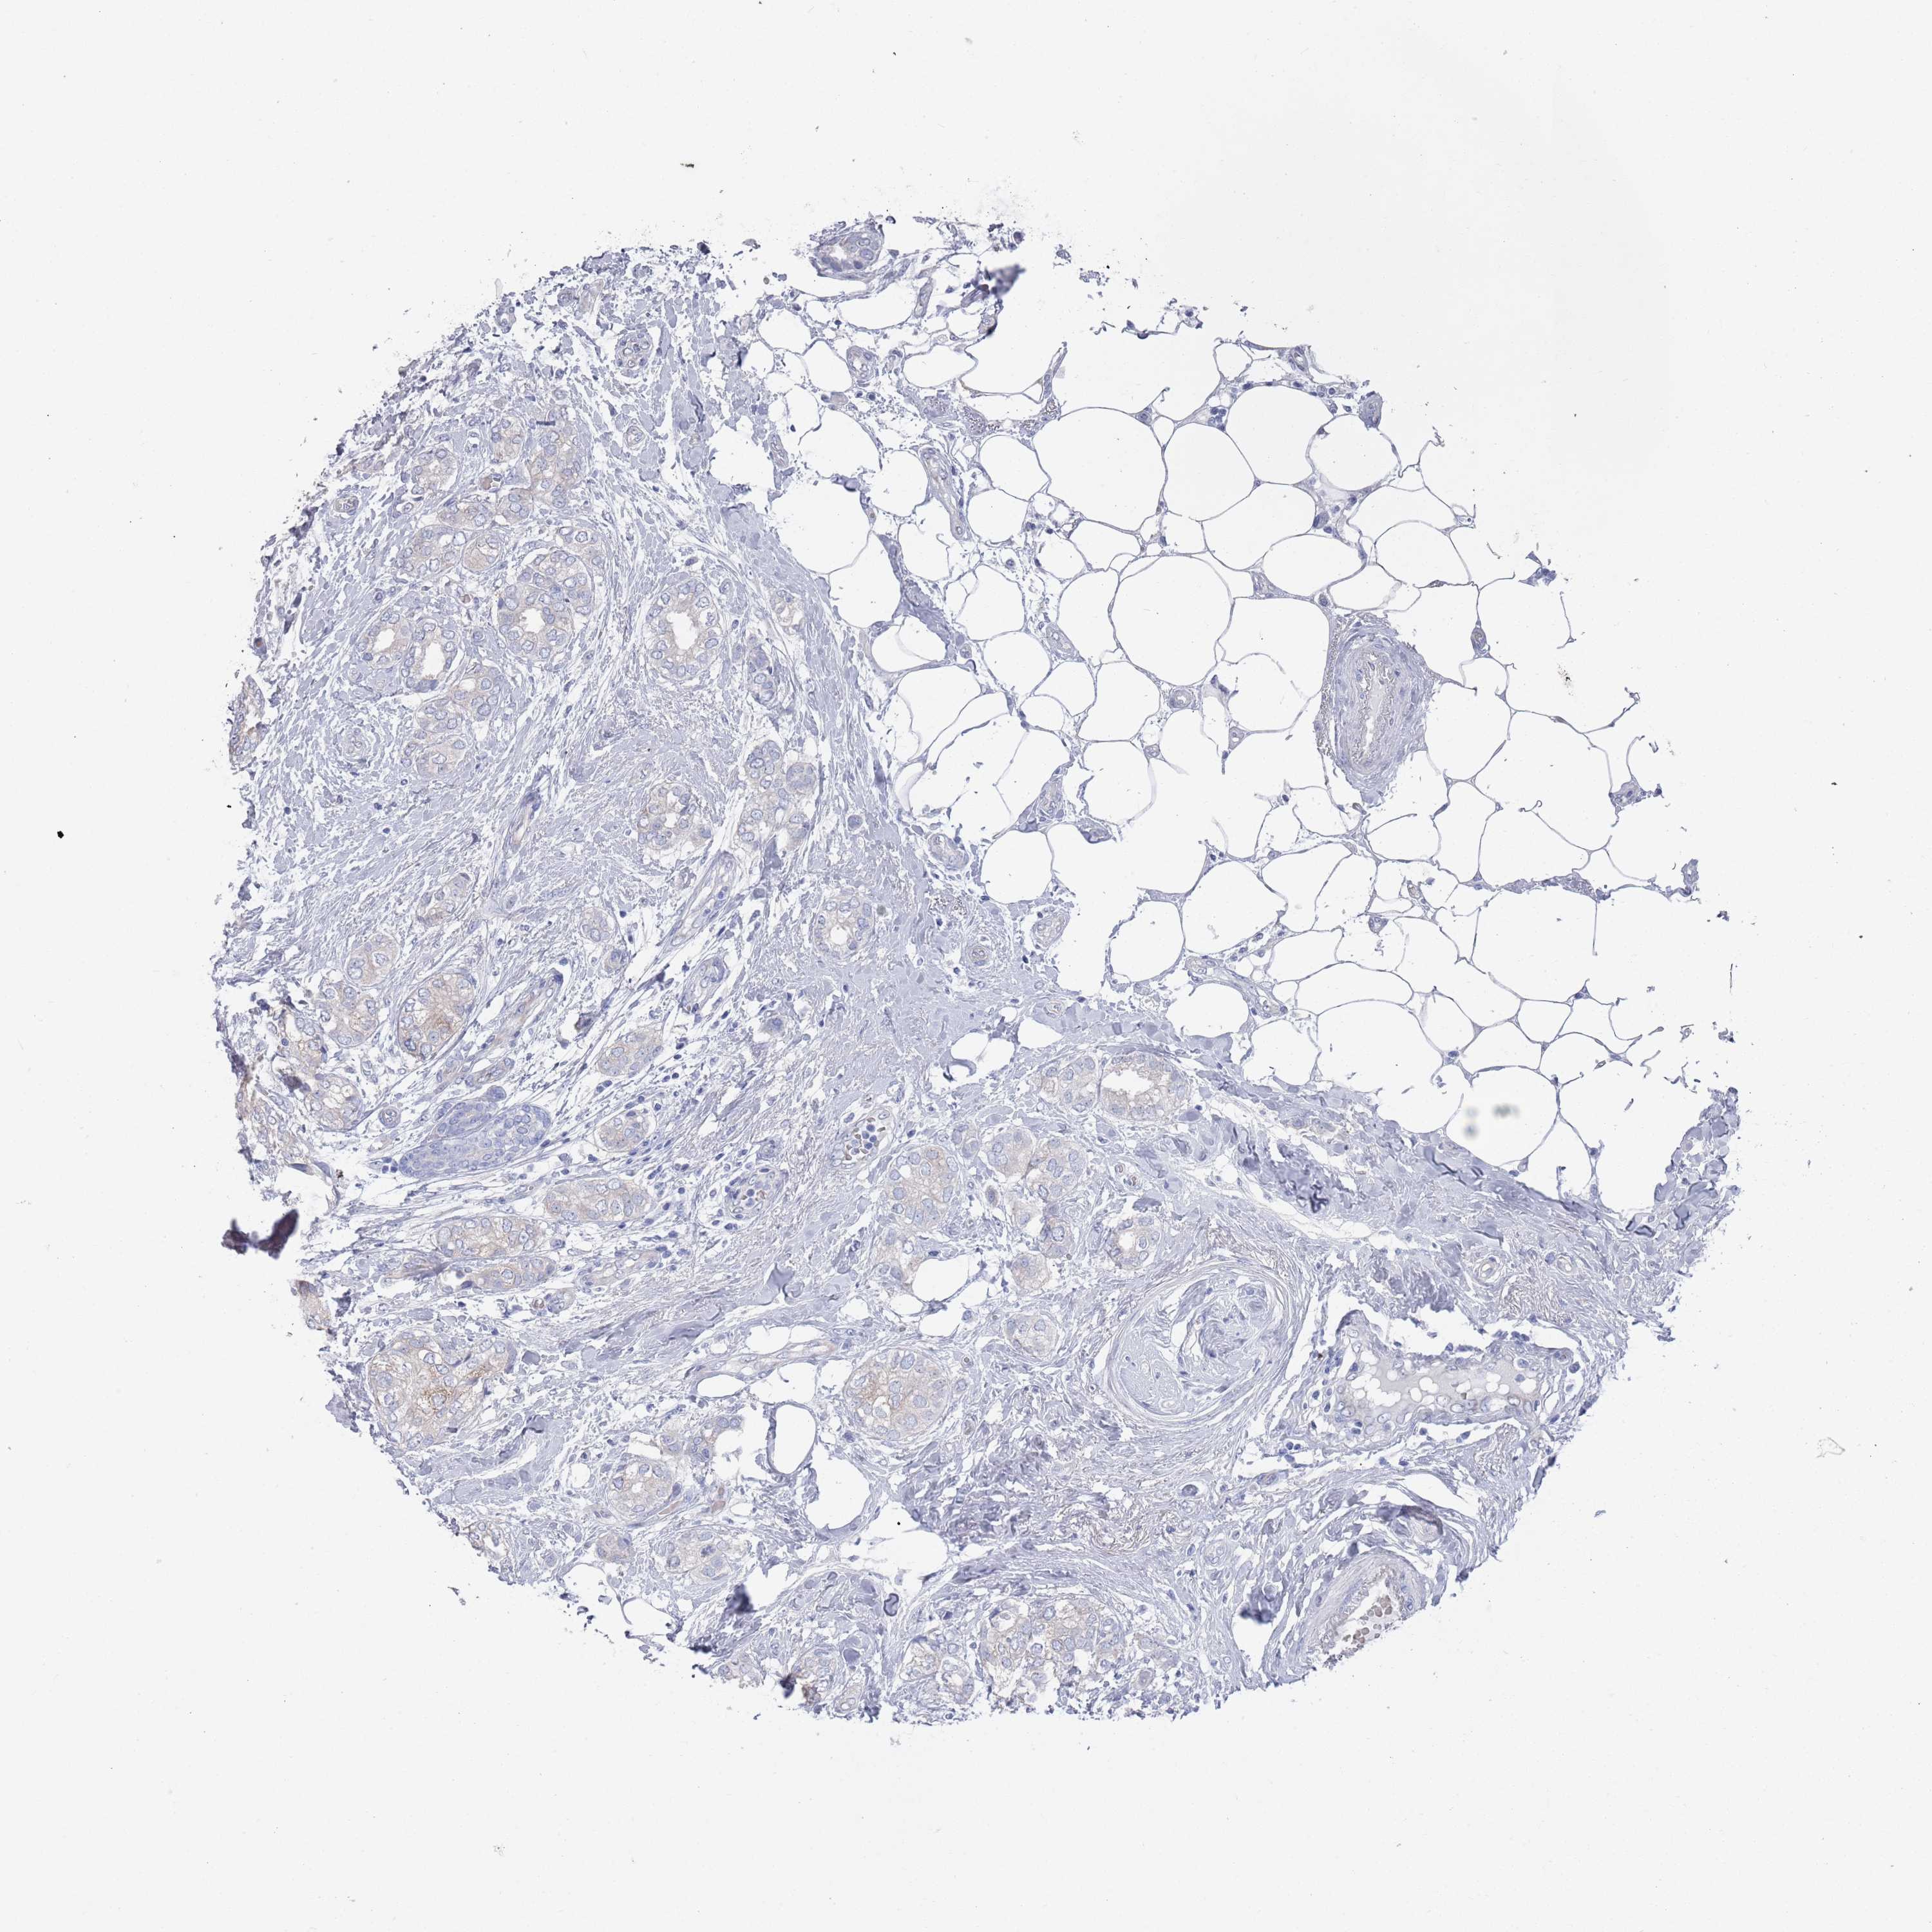

BRCA TCGA BRCA VALIDATION PROTEIN EXPRESSION

ANTIBODIES

AND

VALIDATION